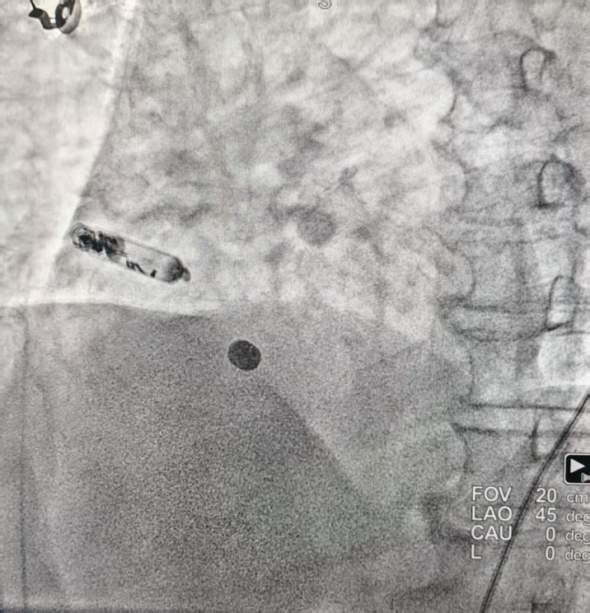

完善相关术前准备,手术由心血管内科蒲晓群教授、江斌主任共同操作。术中经患者大腿根(股静脉)这一微创路径,通过造影确认,精准将心室无导线起搏器植入右心室低位间隔,再将心房无导线起搏器通过递送导管置入右心耳基底部,张力测试后顺利释放。术后患者各项指标良好,i2i通讯流畅,房室同步性表现优异。